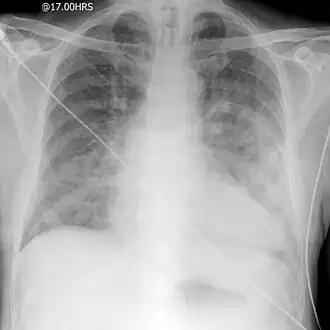

Une radiographie pulmonaire standard permet de rechercher :

- une cardiomégalie, c'est-à-dire une augmentation de taille de la silhouette cardiaque (son absence est possible) ;

- un syndrome alvéolaire ;

- des lignes de Kerley B ;

- parfois un épanchement pleural ;

- des opacités alvéolaires, floconneuses, généralement bilatérales et symétriques, souvent systématisées para-hilaires « en ailes de papillon », parfois diffuses (mais peuvent être unilatérales et asymétriques).